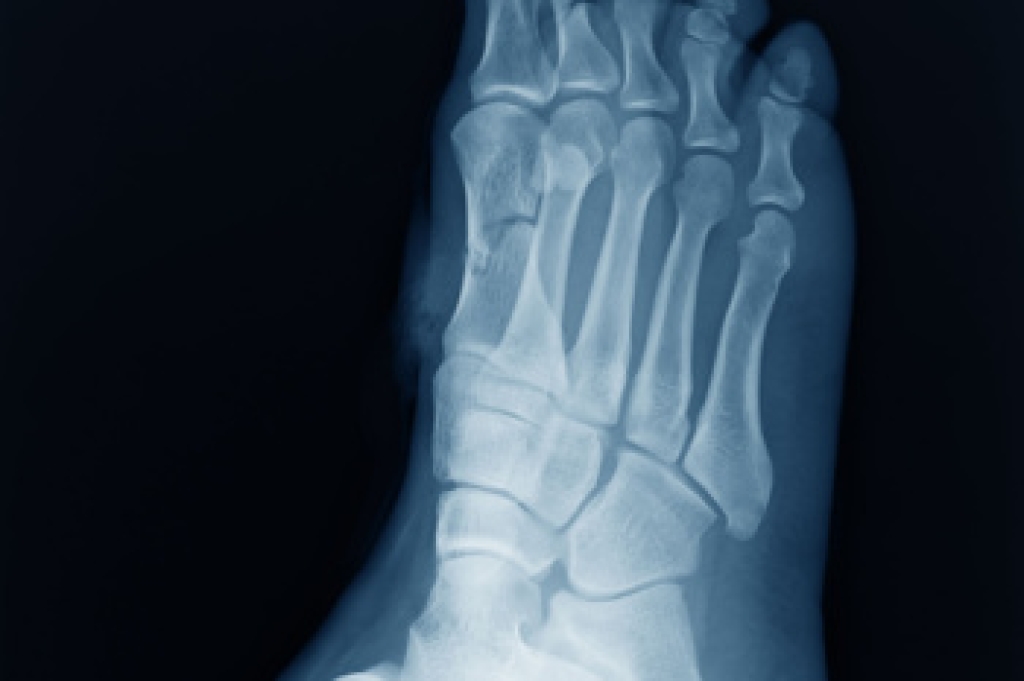

Diagnosis of cuboid syndrome is often difficult, and it is often misdiagnosed. X-rays, MRIs and CT scans often fail to properly show the cuboid subluxation. Although there isn’t a specific test used to diagnose cuboid syndrome, your podiatrist will usually check if pain is felt while pressing firmly on the cuboid bone of your foot.